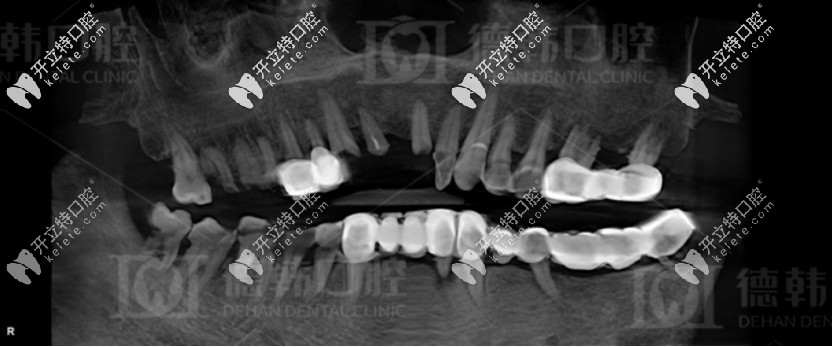

拔牙前爺爺?shù)恼掌?/strong>

沒(méi)有意識(shí)到牙齒缺失不修復(fù)的危害

據(jù)爺爺講述:他剛開(kāi)始跟多數(shù)人一樣,覺(jué)得缺牙沒(méi)啥大不了的,但是后來(lái)在牙齒陸陸續(xù)續(xù)都開(kāi)始松動(dòng)掉落時(shí),才意識(shí)到問(wèn)題的重要性。

德韓口腔先是對(duì)他進(jìn)行了全面的口腔檢查,發(fā)現(xiàn)其患有重度的牙周病,而且爺爺全口牙齒松動(dòng),牙列缺損,上下頜骨重度萎縮,無(wú)法保留口腔里的余牙,只能全部拔掉。

種植前爺爺?shù)难榔?/strong>